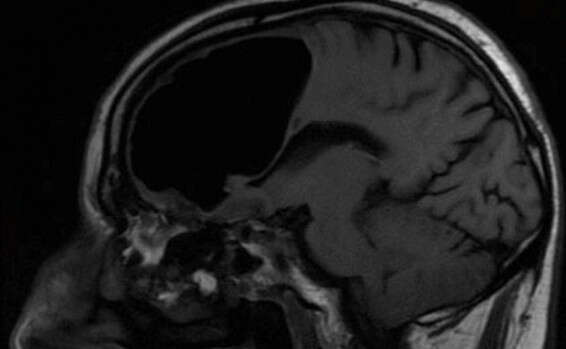

כיס האוויר בראשו של החולה // צילום: טוויטר, BMJCaseReports

הסריקות שביצעו בראשו של החולה גילו ממצא יוצא דופן – כיס אוויר בגודל של 3.5 אינץ' (8 ס"מ). התופעה, המכונה "פנאומטוקל", מתרחשת באונה המצחית, האחראית בין היתר על ביצוען של תנועות גוף.

בסריקת ה-MRI של הפציינט נמצא גם גידול שפיר קטן שגורם לאוויר להיכנס אל תוך מוחו. "זה כמו בבקבוק קולה – לפעמים יש שסתום חד כיווני שמאפשר לאוויר להיכנס ולא לצאת", הסביר ד"ר אלאן כהן, רופא נוירוכירוגי שלא היה מעורב באירוע המדובר.